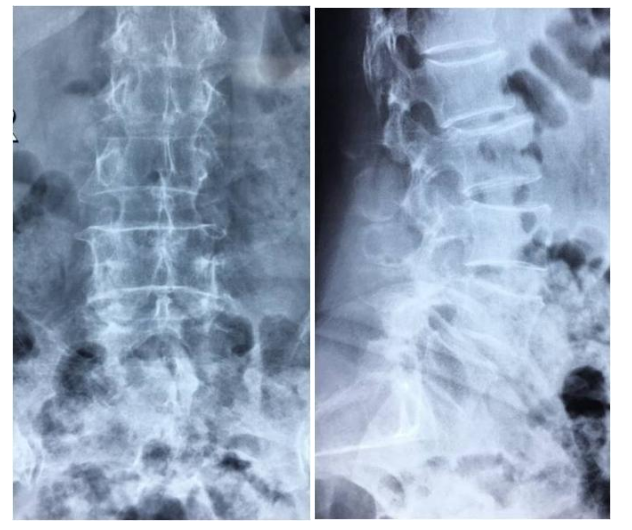

徐XX,女,66岁。

主诉:腰疼及左下肢疼痛麻木半年,加重3个月。

查体:L4-5棘间及椎旁压痛,左下肢直腿抬高试验50度阳性,双下肢肌力肌张力正常。

图1 术前X线片